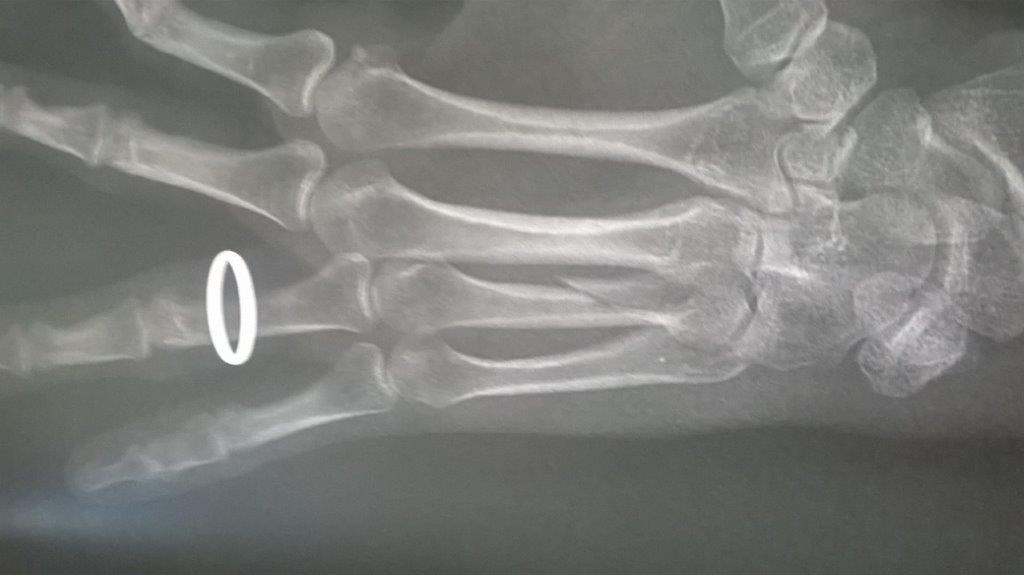

Résultat : fracture de la main gauche

Fichier(s) joint(s):

WP_20170914_001.jpg [ 47.5 Kio | Vu 29201 fois ]

Mais je confirme que ma saison de triathlon s'achève aujourd'hui. Main gauche immobilisé. Je suis au regret de déclarer forfait pour Paladru et d'abandonner les Mixirilliettes à leur triste sort